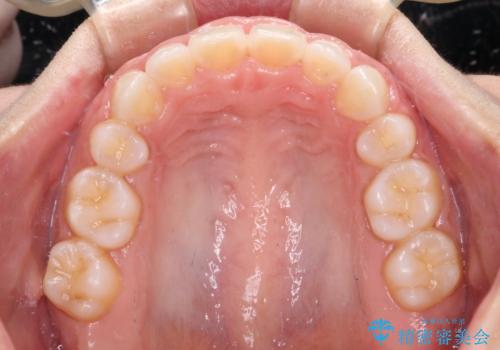

上下顎ともに前突しており、特に上顎は著しい突出感でした。

また、下顎歯列には左右差があり、非対称な抜歯が必要と判断されたため、治療は困難なものとなりました。

それでも根気強く通院してくださり、横からの顔貌の印象が大きく改善され、スムーズに口が閉じられるようになりました。